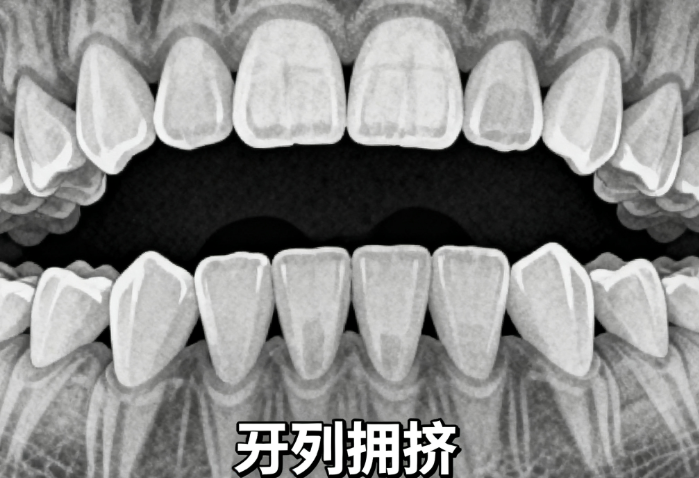

1. 适用于轻中度牙齿拥挤(I-II类),如前牙间隙、轻度龅牙等